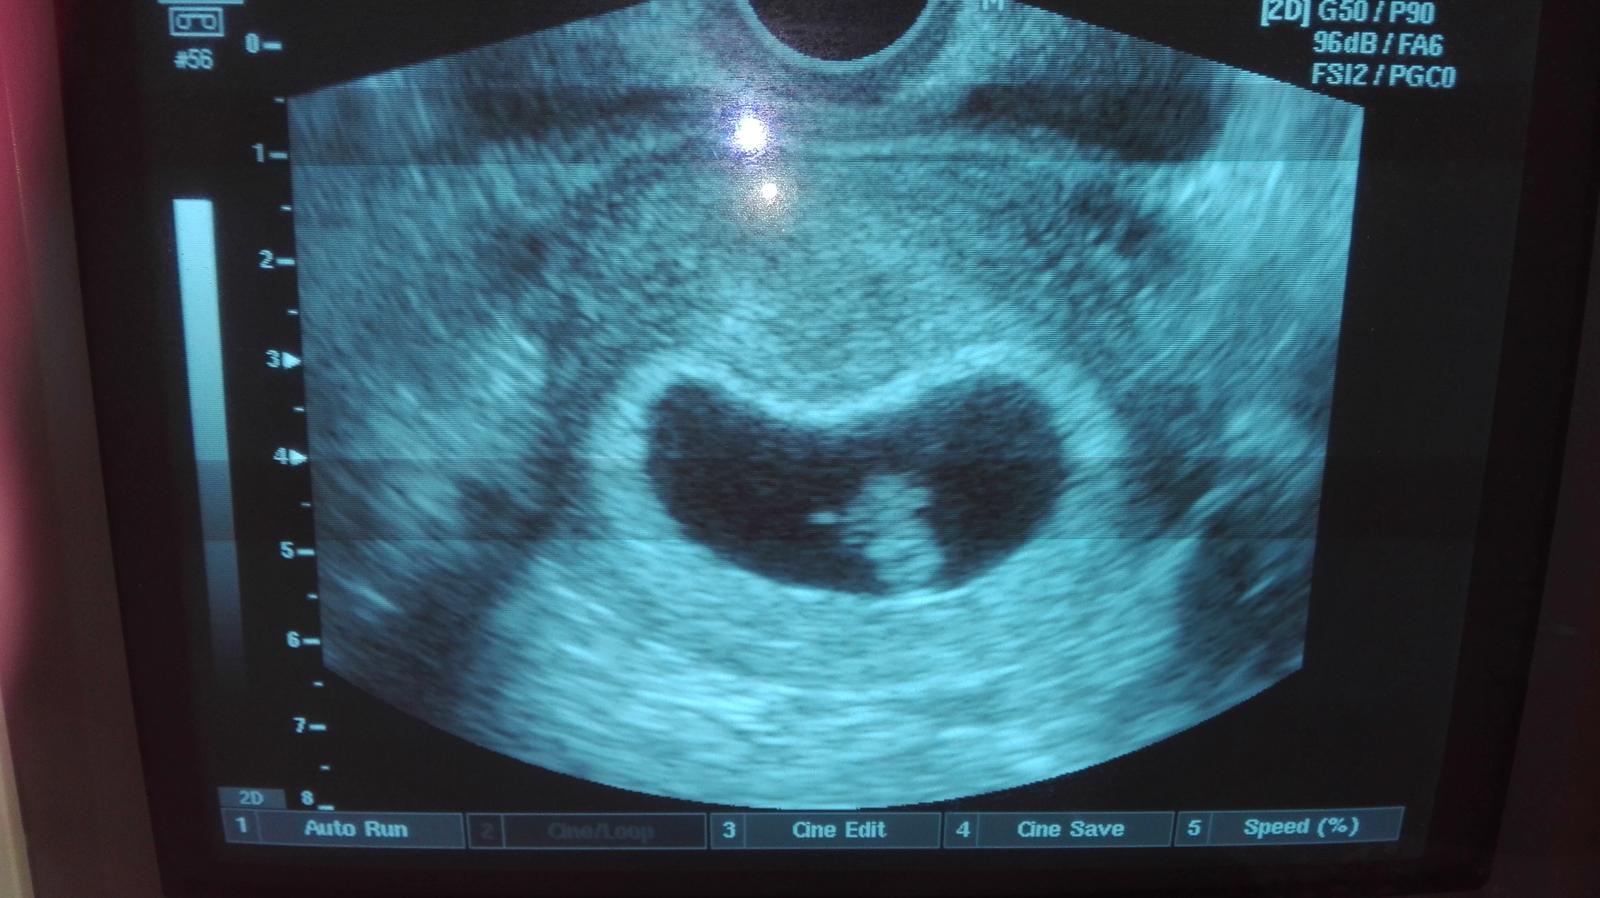

@dancura co je podla teba na uzv plodova voda? Toto je moje 6+1 podla uzv